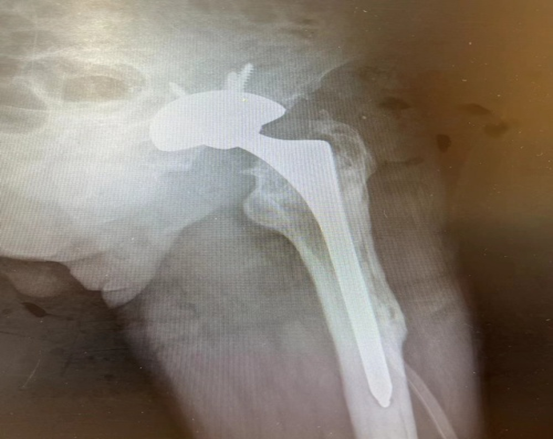

由于充分的术前设计及术中配合,手术顺利。术后,X光拍片显示假体位置满意,双下肢等长。

( 术后X光片 )

术后第二天,拔除引流管后大伯就能下床站立及进行髋关节活动,疼痛感明显减轻,对手术效果非常满意,查房时总是面带微笑,说着感谢的话。出院后,多次电话回访,现在走路基本恢复正常,无明显疼痛,夸奖手术做得好,帮他解决了大问题。